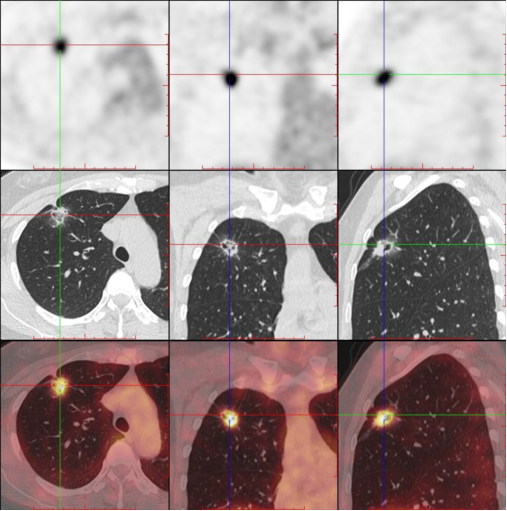

【影像读片】影像读片 肺泡细胞癌?结节病?抑或其它 [病例帖]

细支气管肺泡癌的影像学